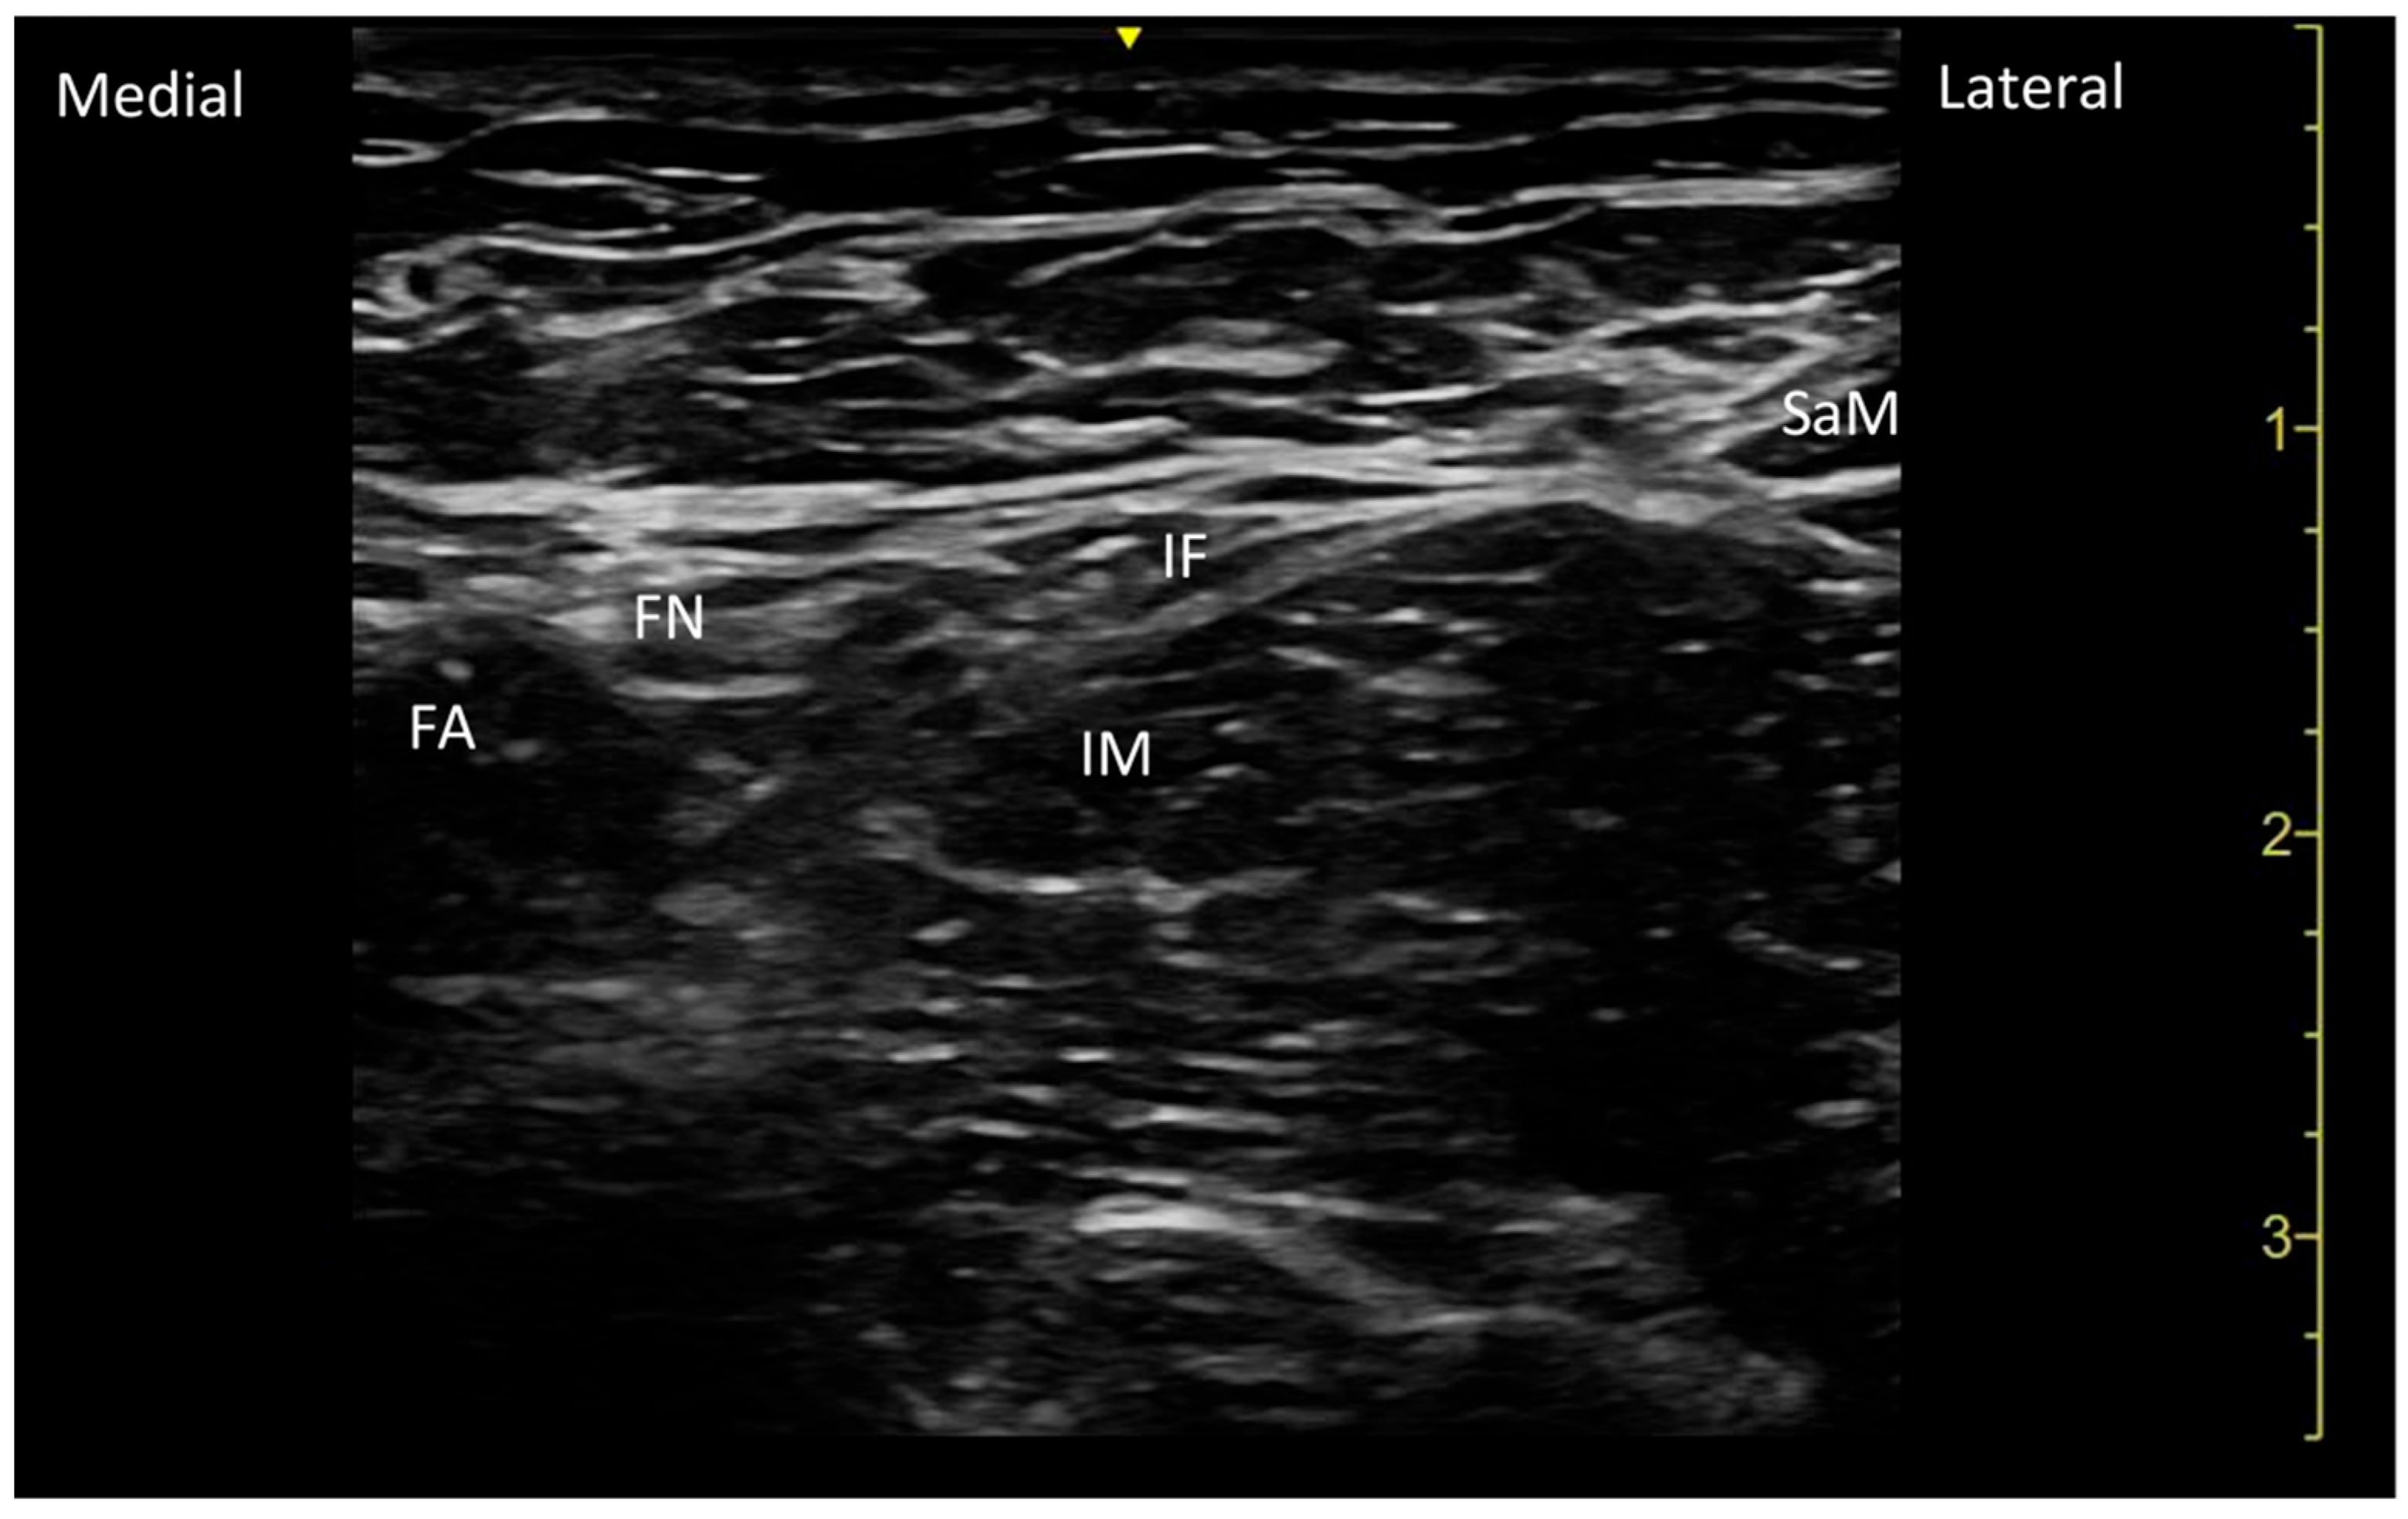

| SaM | Sartorius muscle |